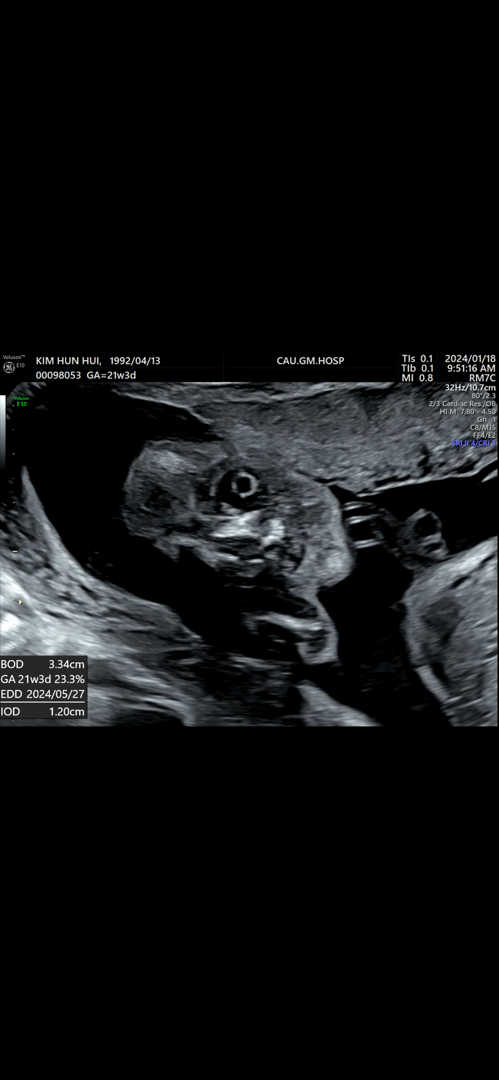

눈뜬 아기.. 얼굴

뱃속에서 저러고 눈크게 뜨고 쳐다보고 있네요. 조곰 무섭게 생겼어여..

저도 그랬어요! 초음파로 투과해서 보는거라 쌤이 눈동자라고 알려주셨어요 ㅎㅎ